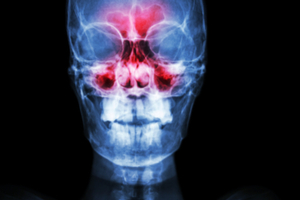

The Sinus X-ray, also known as a paranasal sinus X-ray or simply a sinus radiograph, is a diagnostic imaging test used to capture detailed images of the sinus cavities. This exam helps assess the presence of sinusitis, blockages, structural abnormalities, or infections in the paranasal sinuses, which are the air-filled spaces within the bones surrounding the nose. By using low-dose radiation, this X-ray creates clear images that aid in diagnosing conditions related to the sinuses.

The Sinus X-ray (Paranasal) is used to help diagnose and monitor conditions such as sinusitis (inflammation of the sinuses), nasal polyps, structural abnormalities like a deviated septum, and chronic rhinitis. It is also beneficial for detecting sinus infections and cysts that may cause prolonged discomfort. Additionally, sinus X-rays are used to evaluate facial trauma that might have impacted the sinus cavities or to check for signs of rare conditions such as sinus tumors.